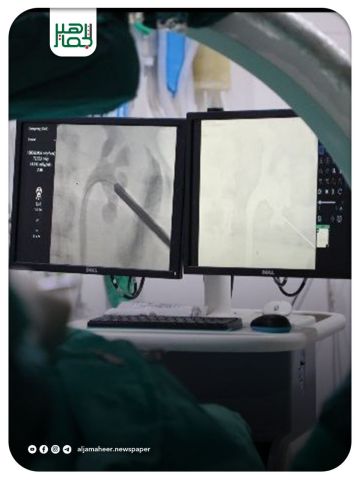

تمكّن جراحو مشفى الشفاء من استخراج حصاة بحجم 5 سم باستخدام تقنية (PCNL) عبر الجلد، دون أي تدخل جراحي، لشاب يبلغ من العمر 39 عاماً من كليته اليسرى، والتي كانت تسبب له آلاماً مبرحة على مدى فترة طويلة.

وغادر الشاب المشفى بعد 16 ساعة فقط وهو بحالة صحية جيدة، دون تسجيل أي مضاعفات تُذكر.

ويُعد تطبيق تقنية (PCNL)، وهي إحدى أحدث الإجراءات الطبية المتقدمة، إنجازاً جديداً يُضاف إلى سلسلة إنجازات كوادر مشفى الشفاء.

وجدير بالذكر أن تكلفة هذه التقنية الحديثة والمتطورة مرتفعة، إلا أنها تُقدَّم مجاناً في مشفى الشفاء التابع لمديرية صحة إدلب، دعماً للمرضى وتخفيفاً عنهم من أعباء التكلفة ووقت الاستطباب والمعالجة.